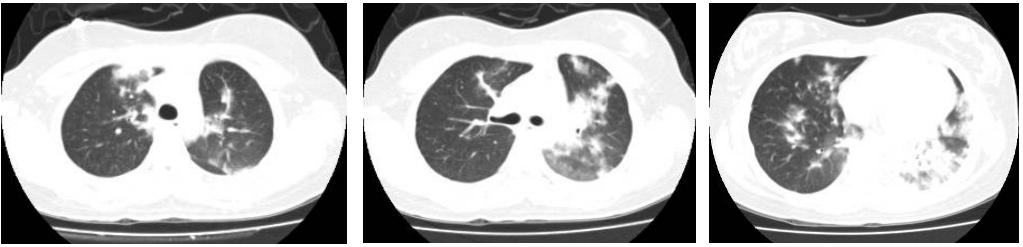

这是广州呼吸健康研究院的一个病例。17岁的女孩,发热4天、气促1天,2009年11月25日入院。胸部CT显示肺炎,WBC:3.6×10^9/L,H1N1 PCR:阳性。SPO2 90%(鼻导管氧疗3L/min)。

这时使用鼻罩CAPA治疗,5cm H2O,连续不间断使用3天后开始改善。随后改为间歇使用鼻罩CPAP 3天,总共6天。症状改善、耐受性好,P/F改善到320mmHg,最终康复出院。我们的应用体会是,对此类患者,NIV治疗需要时持续不间断使用,直到病情缓解后才过渡到间歇使用。